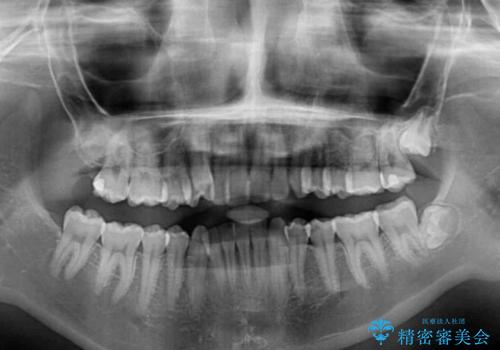

片側の八重歯であり上顎の正中がずれていたため、上顎左右第一小臼歯2本を抜歯して排列することとしました。

下顎の骨格的なズレが大きかったため、上下歯列のバランスが取れるか心配でしたが、上下ともに左右対称に近い歯列で治療を終えることができました。